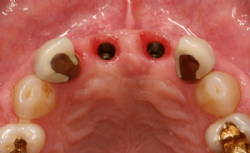

Abbildung 2: Situation von okklusal vor und nach der Augmentation

Implantation

Drei Monate nach der Augmentation wurden zwei Astra®-Implantate (Durchmesser 4.5 mm, Länge 13 mm) gesetzt. Während der Einheilphase von knapp fünf Monaten wurden die Implantate nicht belastet, die Implantate heilten gedeckt ein.

Abbildung 3: Astra-Implantate am Ende der Einheilphase